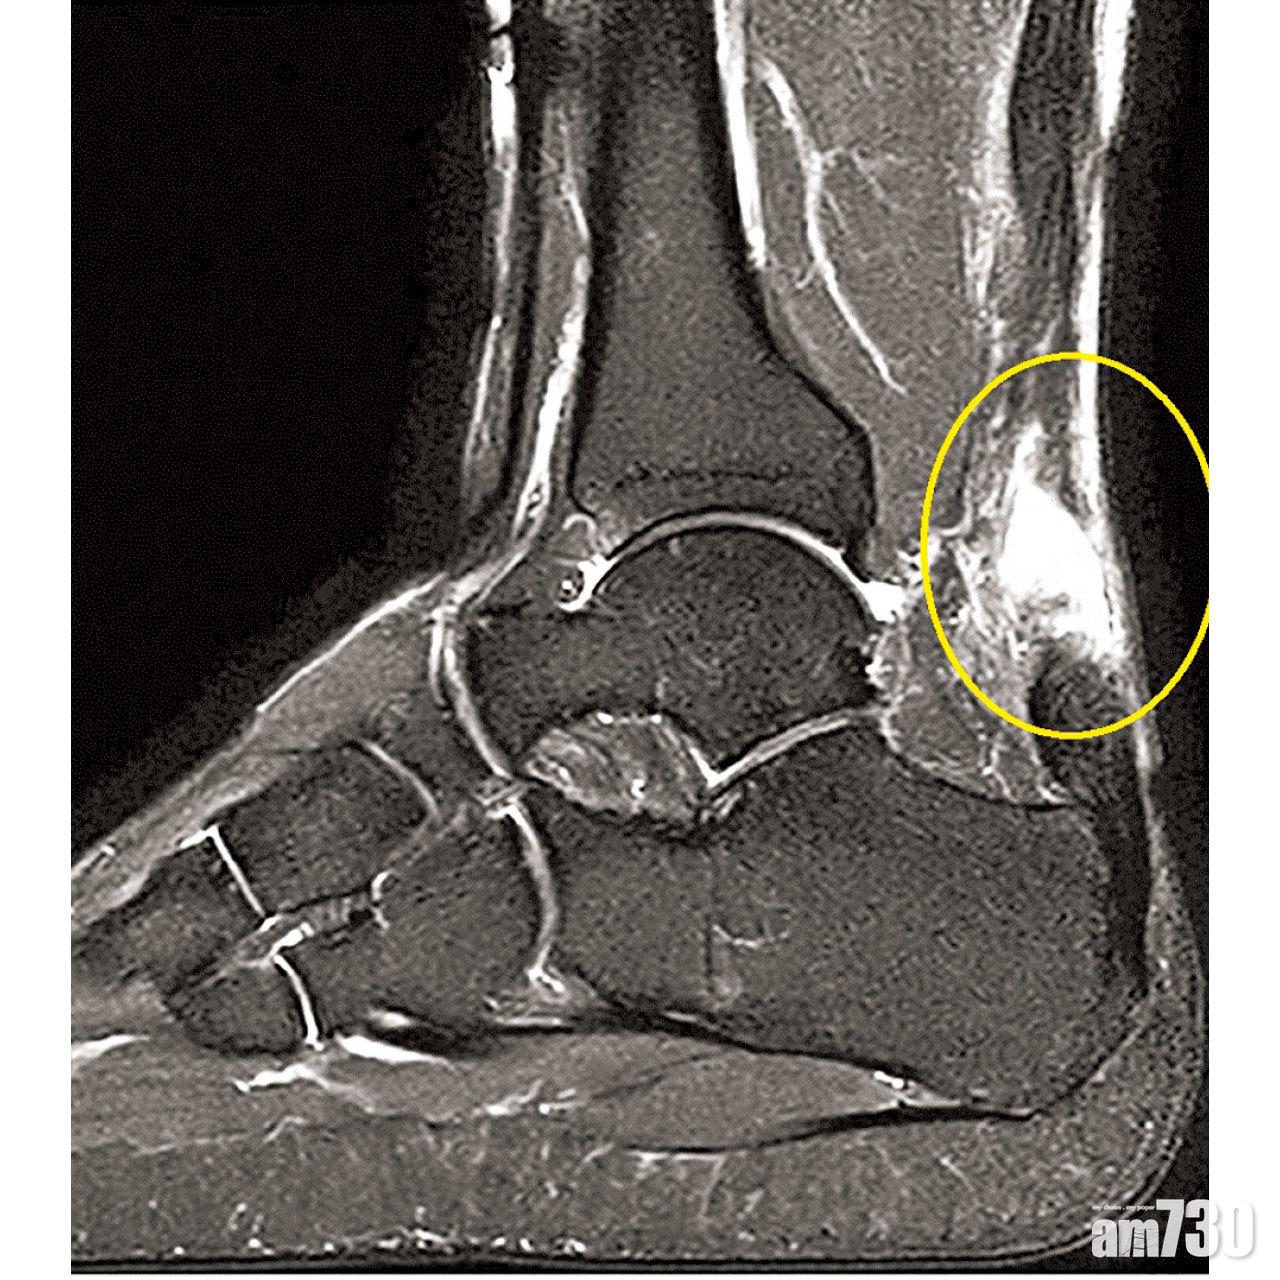

一旦跟腱斷裂,傷者會感到腳踭刺痛和出現腫脹;當走路時,亦不能再發力提起腳踭以腳尖站立。跟腱斷裂雖屬臨床診斷,但磁力共振能確定斷裂的位置和嚴重性,以及跟腱本身有沒有因勞損而出現病變。過往在治療跟腱斷裂上,可選擇打石膏固定足踝在蹠屈姿勢,讓跟腱自然愈合。惟近年骨科醫生大多傾向做微創手術來修補跟腱,以加速復康進度並減低跟腱再斷裂的風險。